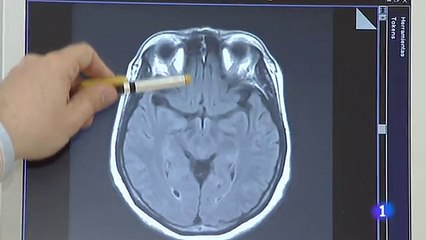

El otorrinolaringólogo Adrian Simes explica porque el coronavirus provoca la pérdida de olfato, cuanto puede durar y cómo hacer para recuperarlobr br LT